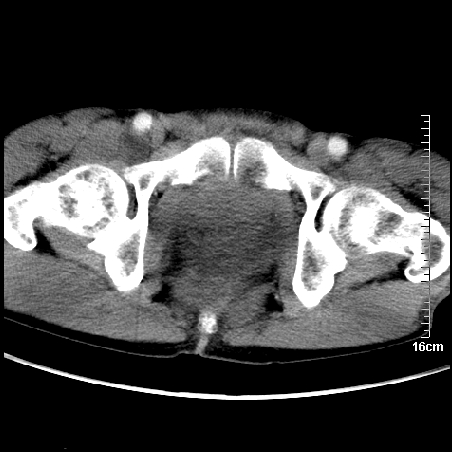

增强:

1、骶尾部巨大软组织肿块,部分骶尾骨以被软组织肿块代替,呈不规则侵蚀;病变突向盆腔内;增强扫描病变呈不均质强化;首先考虑脊索瘤。不支持的一点就是病变内无钙化。

2、发生于骶尾椎者须与骨巨细胞瘤鉴别,骨巨细胞瘤一般发在上疗骶椎,肿瘤内无钙化,一般无侵袭性生长的表现。